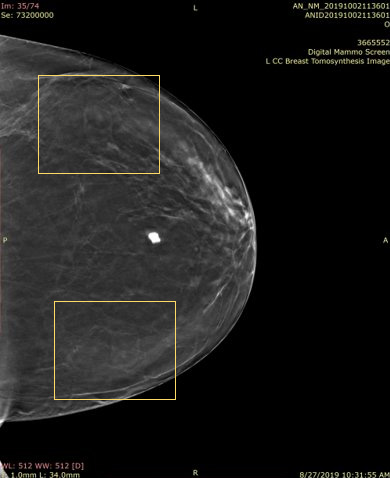

Architectural Distortion On 3d Mammogram

Pdf Detection Of Masses And Architectural Distortions In Digital Breast Tomosynthesis Images Using Fuzzy And A Contrario Approaches Semantic Scholar